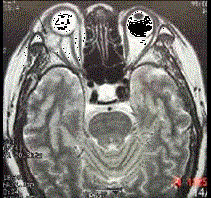

问题 男性,41岁,右侧眶外上方肿胀,可触及无痛性包块,CT及MRI检查如图所示,请选择最可能诊断 ( )

选项 A、泪腺混合瘤 B、眶内囊肿 C、眶内结核 D、眶内炎性假瘤 E、眶内血管瘤

答案 A